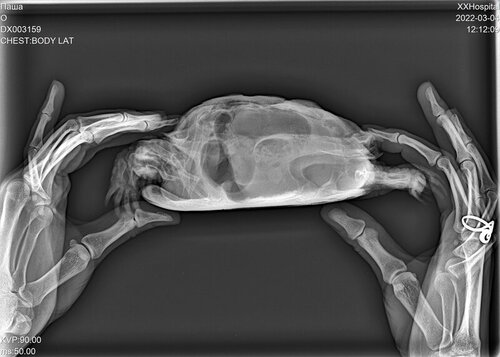

черепаха среднеазиатская, 14см, пол М

Жалобы: начал окрывать рот и запрокидовать голову, раздулся сильно.

состояние не улучшается, но рот открывать и запрокидывать голову перестал, дышит ровно, отечность сохраняется преимущественно слева.

при передвижении задние лапы не использует, но отдельно ими шевелить может. Ест листовой салат. Опоржение происходит жидкостью после введения препаратов. Лапы достаточно сильные - слабости у питомца не наблюдается

Лечение на фото, рентген, фото сегодня. Все фото прикреплю в комментариях

DX003159_2.JPG